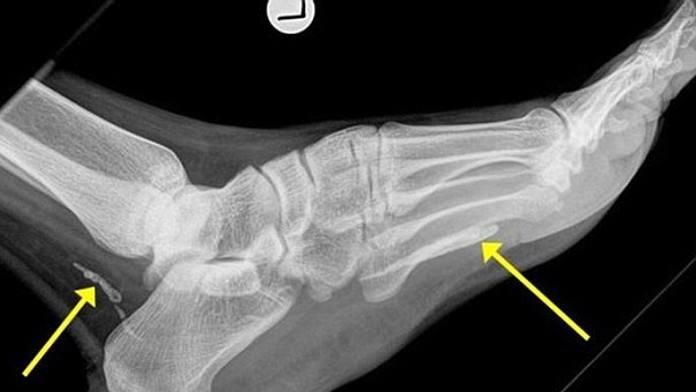

Lekári mu na to prišli až po štyroch rokoch.

Nemal ani potuchy, čo mal štyri roky vo vnútri jeho tela. V nohe mal meter dlhého afrického červa. Podľa lekára tam tvor prednedávnom zomrel a bol pochovaný na zadnej strane členka. Mladík musel preto podstúpiť operáciu, aby mu nebezpečný parazit nespôsobil smrť.

Tieto červy žijú podľa odborníkov najmä v črevách. Tam sa dostanú ešte ako larvy cez pitnú vodu alebo potravu. Konkrétne tento sa prekopal do tela muža cez krvavý pľuzgier na koži.